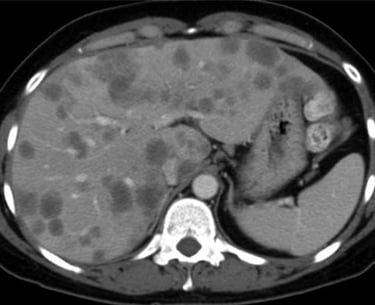

O câncer colorretal frequentemente se espalha para o fígado, e a metástase hepática é uma complicação comum e séria. A intervenção cirúrgica desempenha um papel crucial no manejo dessas metástases. O tratamento cirúrgico pode oferecer uma chance significativa de cura ou prolongamento da sobrevivência para pacientes com metástases hepáticas ressecáveis.

Tratamento Cirúrgico das Metástases Hepáticas

Ressecção Hepática Metastática: A remoção cirúrgica das áreas do fígado afetadas por metástases colorretais. Pode ser realizada em pacientes com um número limitado de metástases e função hepática adequada.

Terapias Combinadas: A cirurgia é frequentemente combinada com quimioterapia neoadjuvante (antes da cirurgia) para reduzir o tamanho das metástases, ou adjuvante (após a cirurgia) para eliminar células cancerígenas remanescentes.

Abordagens Minimamente Invasivas: Procedimentos como a ablação por radiofrequência podem ser usados para tratar pequenas metástases, especialmente em pacientes que não são candidatos à cirurgia aberta.

A Importância do Tratamento Cirúrgico

A cirurgia oferece a melhor chance de cura para pacientes com câncer de fígado em estágio inicial e para aqueles com metástases hepáticas de câncer colorretal ressecáveis. A remoção completa do tumor ou das metástases pode levar à remissão da doença e melhorar significativamente a qualidade de vida do paciente. Mesmo em casos avançados, a cirurgia pode ajudar a controlar os sintomas e prolongar a sobrevivência.

O câncer de fígado e as metástases hepáticas do câncer colorretal são condições graves que requerem diagnóstico precoce e tratamento adequado. A cirurgia é uma abordagem fundamental no tratamento dessas doenças, oferecendo a melhor chance de cura e controle da doença. Pacientes devem estar atentos aos sinais e sintomas e procurar atendimento médico imediatamente se houver suspeita de problemas hepáticos. Consultas regulares e exames de rotina são essenciais para a detecção precoce e o tratamento eficaz. Se você tiver qualquer sintoma ou preocupação, não hesite em buscar orientação médica.